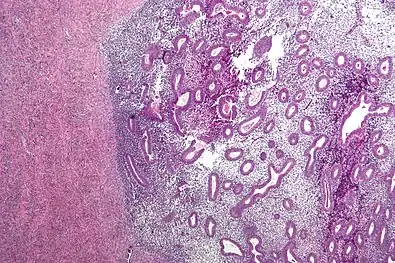

Endometriosis, abdominal wall

Micrograph showing endometriosis (right) and ovarian stroma (left)

Histopathology

For a histopathological diagnosis, at least two of the following three criteria should be present:[110]

- Endometrial type stroma

- Endometrial epithelium with glands

- Evidence of chronic hemorrhage, mainly hemosiderin deposits

Immunohistochemistry has been found to be useful in diagnosing endometriosis as stromal cells have a peculiar surface antigen, CD10, thus allowing the pathologist go straight to a staining area and confirm the presence of stromal cells and sometimes glandular tissue is identified that was missed on routine H&E staining.[111]